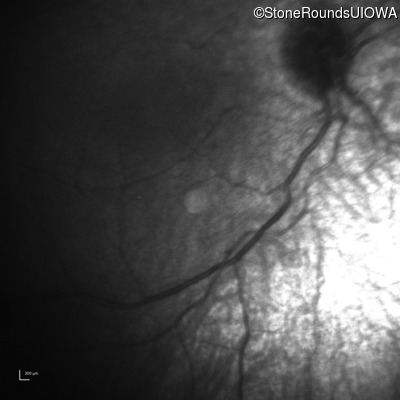

Infrared Fundus Photograph - Right -

No Light Perception

Exemplar

Infrared Fundus Photograph - Left -